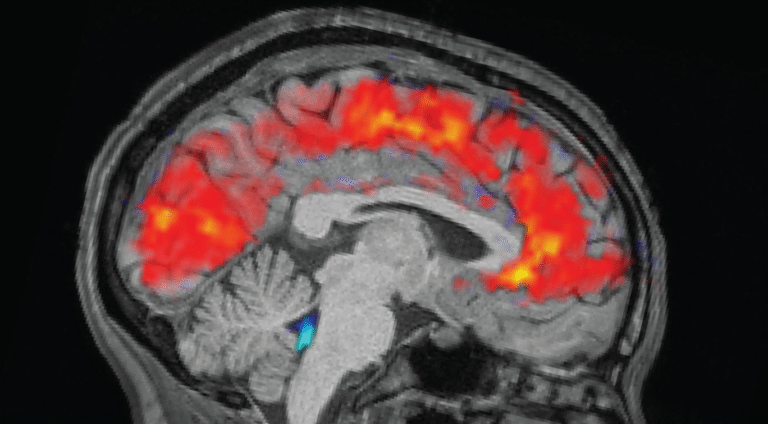

Scientists spot brains zoning out in real time

Ever get that feeling — say, at the end of the week — when you really want to pay attention to something important, but you just zone out and see people’s lips moving?

Well, scientists finally have a physiological explanation for why this happens when you’re sleep-deprived: Your brain is literally flushing out cerebrospinal fluid, making it nigh-impossible for you to concentrate. The exact functional reason for this is still unclear, but scientists think it could have something to do with sleep-deprived brains switching into sleep-like states, possibly as a form of waking brain waste disposal you missed out on the night before.